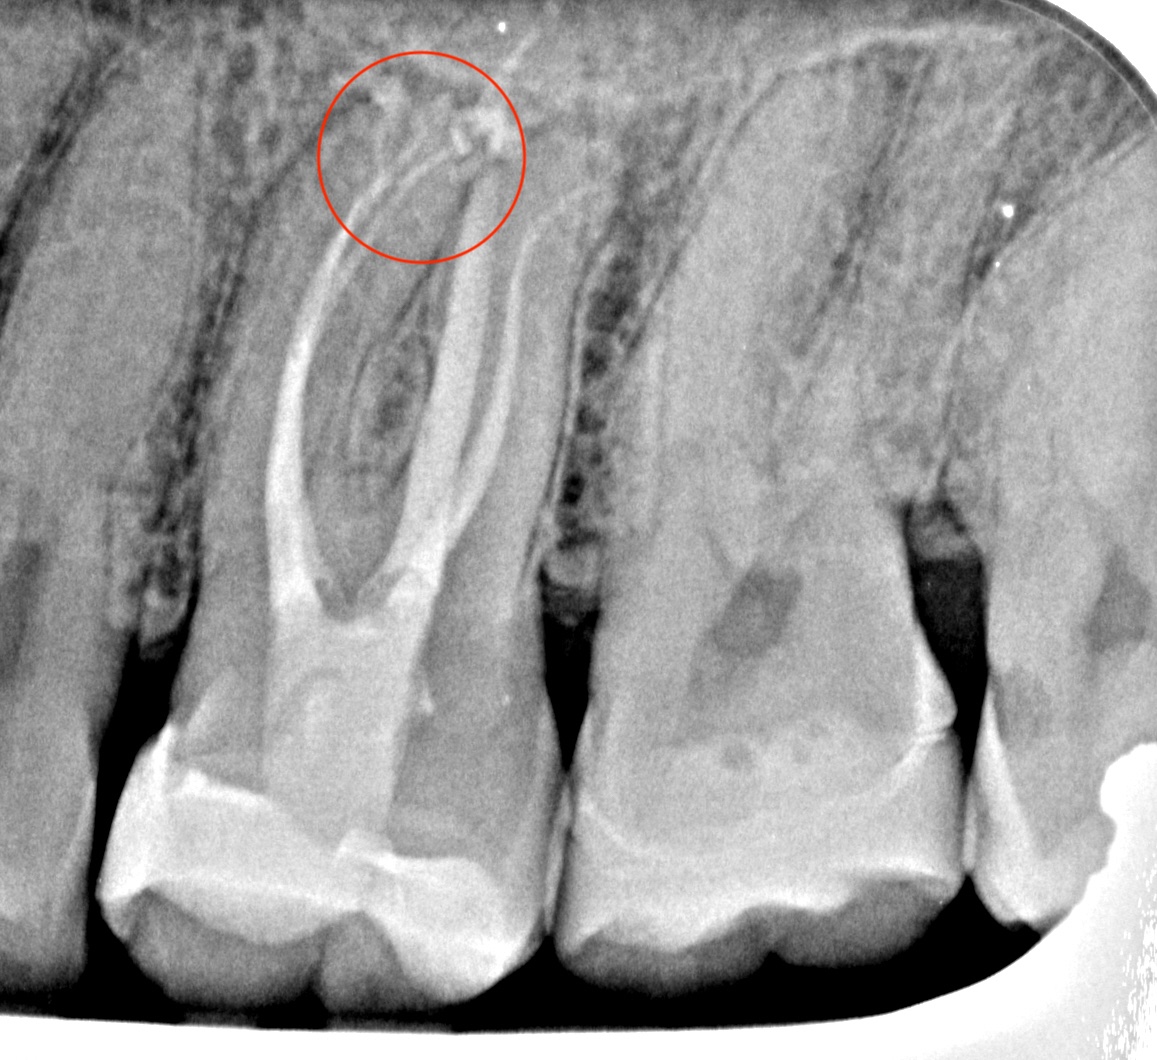

Conservative Access and Root Canal Preparation on a Curvy Molar with 4 Portals of Entry and 5 Portals of Exit

Hybrid sequence of MiniKut 1503, TS 1802, TS 2004 in mb1, mb2 and db. The palatal was finished with a VDW Rotate 3004. This sequence was chosen to suit the narrow-calcified canals. It enabled slow and gradual enlargement of the canals which reduce the chance of the file breakage especially in the distobuccal canal with the ‘s’ shaped curve.

Irriflex and Sodium Hypochlorite (5.25%) throughout with a penultimate rinse with 17% EDTA for 1 minute then back to sodium hypochlorite for a final clean. All irrigants activated with the Eighteeth Ultra X (PUI).

Obturated with

Hydraulic condensation with TotalFill BC sealer Hiflow.